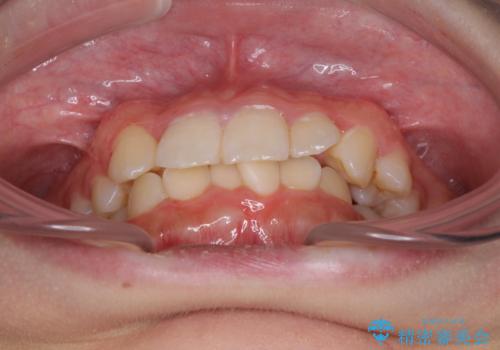

インビザラインが続けられない ワイヤー矯正での抜歯矯正 その2

- 八重歯やデコボコをインビザラインで治療したいとのことで来院された患者様です。

インビザライン単体で治療を行うには叢生が強いと判断されたため、事前にワイヤー装置で抜歯矯正を行い、ある程度改善してからインビザラインにて仕上げていくこととしました。